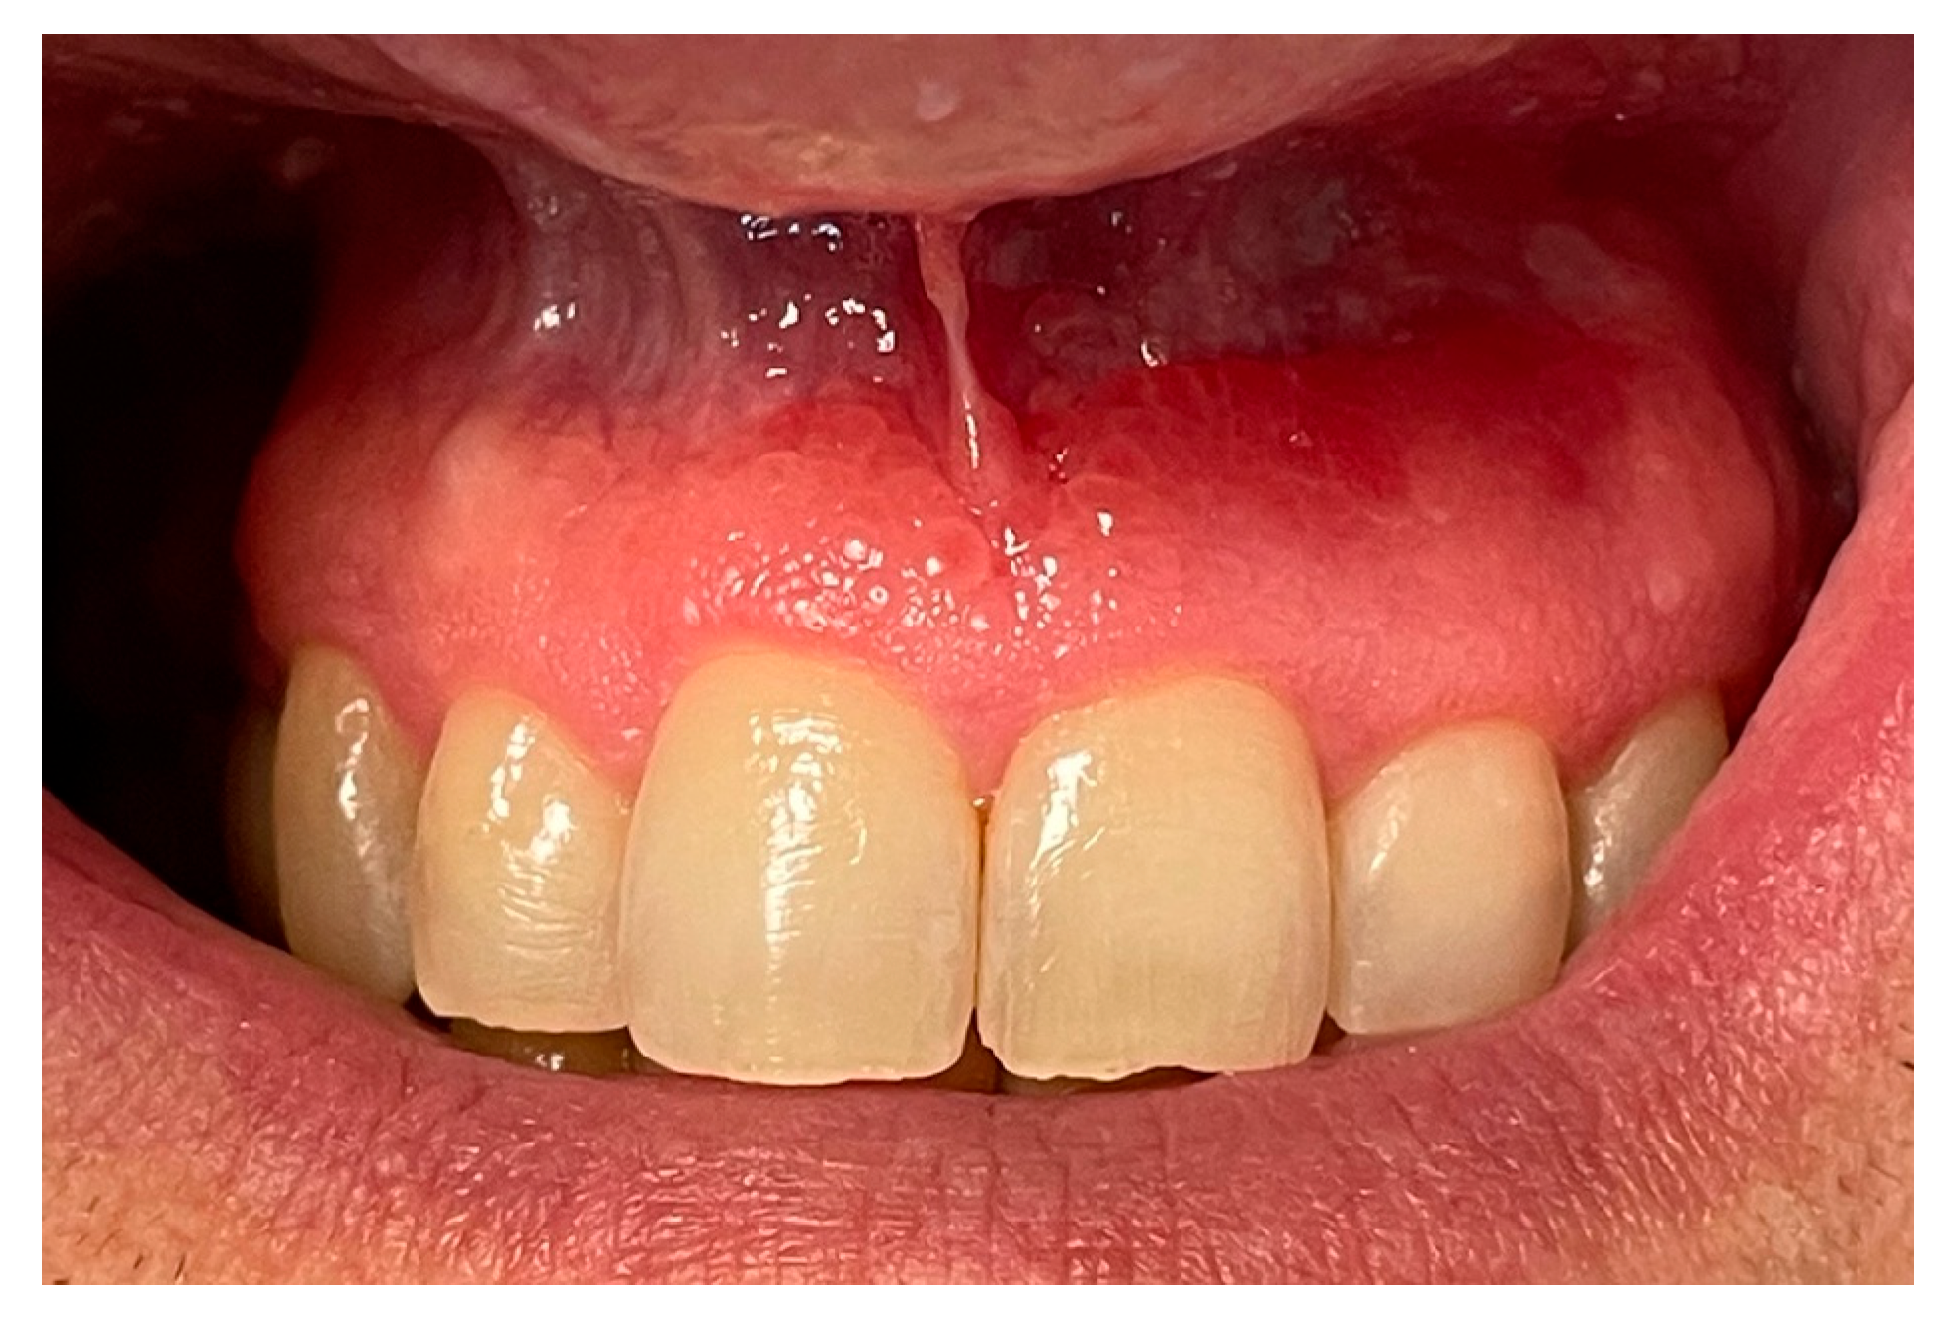

Figure 2. Close-up view showing the extension of the lesion involving the marginal and attached gingiva, as well as the adjacent oral mucosa, with an irregular surface texture and loss of stippling.

Diagnosis of PCG was based on intraoral findings characterized by an erythematous gingiva with loss of stippling [14]. First oral examinations performed and described by Leuci et al. [1] allowed clinicians to detect lesion characteristics in 40 out of 45 cases, specifying the predominant clinical phenotype or provisional diagnosis for each. Among these groups, 25 cases (62.5%) were identified as bullous or nonspecific blistering mucositis, 4 cases (10%) were classified as erythematous lesions consistent with erythroplakia, 4 cases (10%) as keratotic lesions resembling oral lichenoid conditions, 4 cases (10%) as verruciform lesions with features suggestive of malignancy, and 3 cases (7.5%) as ulcerative lesions of indeterminate etiology [1]. In this case report, the lesion appeared polypoid, erythematous, and edematous at the baseline.